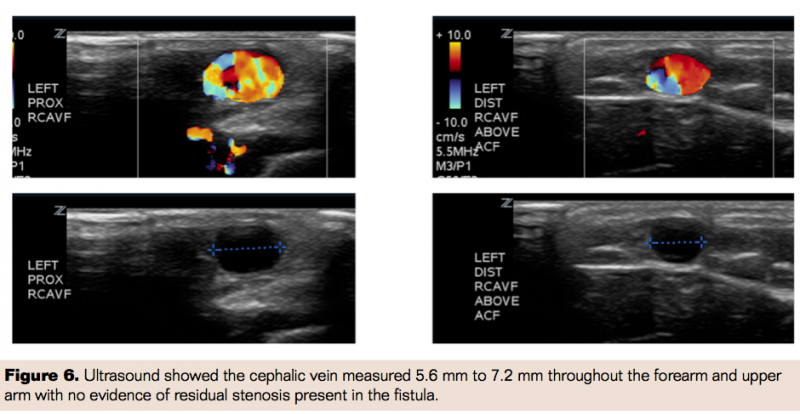

Excellent thrill and bruit were demonstrated at completion of the procedure throughout the cephalic vein. At 1 week postoperative visit, physical exam revealed excellent bruit and thrill throughout the AVF. The cephalic vein measured 5.6 mm to 7.2 mm throughout the forearm and upper arm on ultrasound. There was no evidence of residual stenosis present in the fistula (Figure 6).